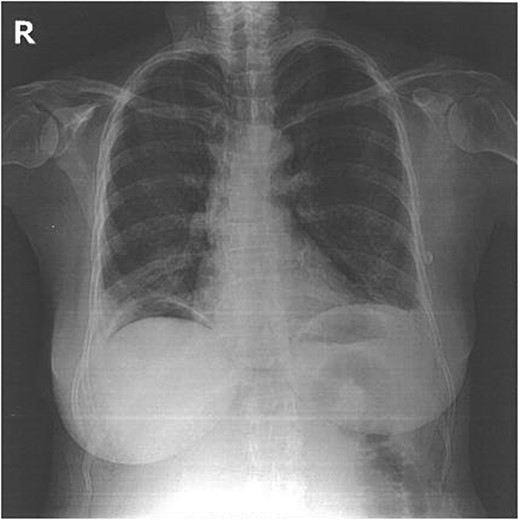

She was placed in a left lateral decubitus position and a posterolateral thoracotomy in the fifth right intercostal space was used. The wire was removed without complications. Surprisingly, no injury was noted to any intervening abdominal structure intra-operatively. As a precaution, a 28-F chest tube was placed. There was no air leak or bleeding postoperatively and the tube was removed on the second postoperative day. The postoperative outcome was favorable and the patient was discharged on postoperative Day 4 with a normal chest radiogram (Fig. 2).